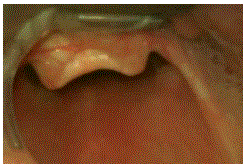

Homem de 70 anos é trazido ao Pronto-Socorro com acidente vascular encefálico isquêmico. Em 48 horas, o paciente evoluiu com rebaixamento do nível de consciência (escala de coma de Glasgow = 8) e vômitos, mantendo pupilas isocóricas, sendo indicada intubação orotraqueal.

Durante a laringoscopia direta realizada com posicionamento ótimo por operador experiente, observou-se a seguinte visualização glótica.

Dentre as alternativas abaixo, a conduta mais adequada neste momento é a intubação com: